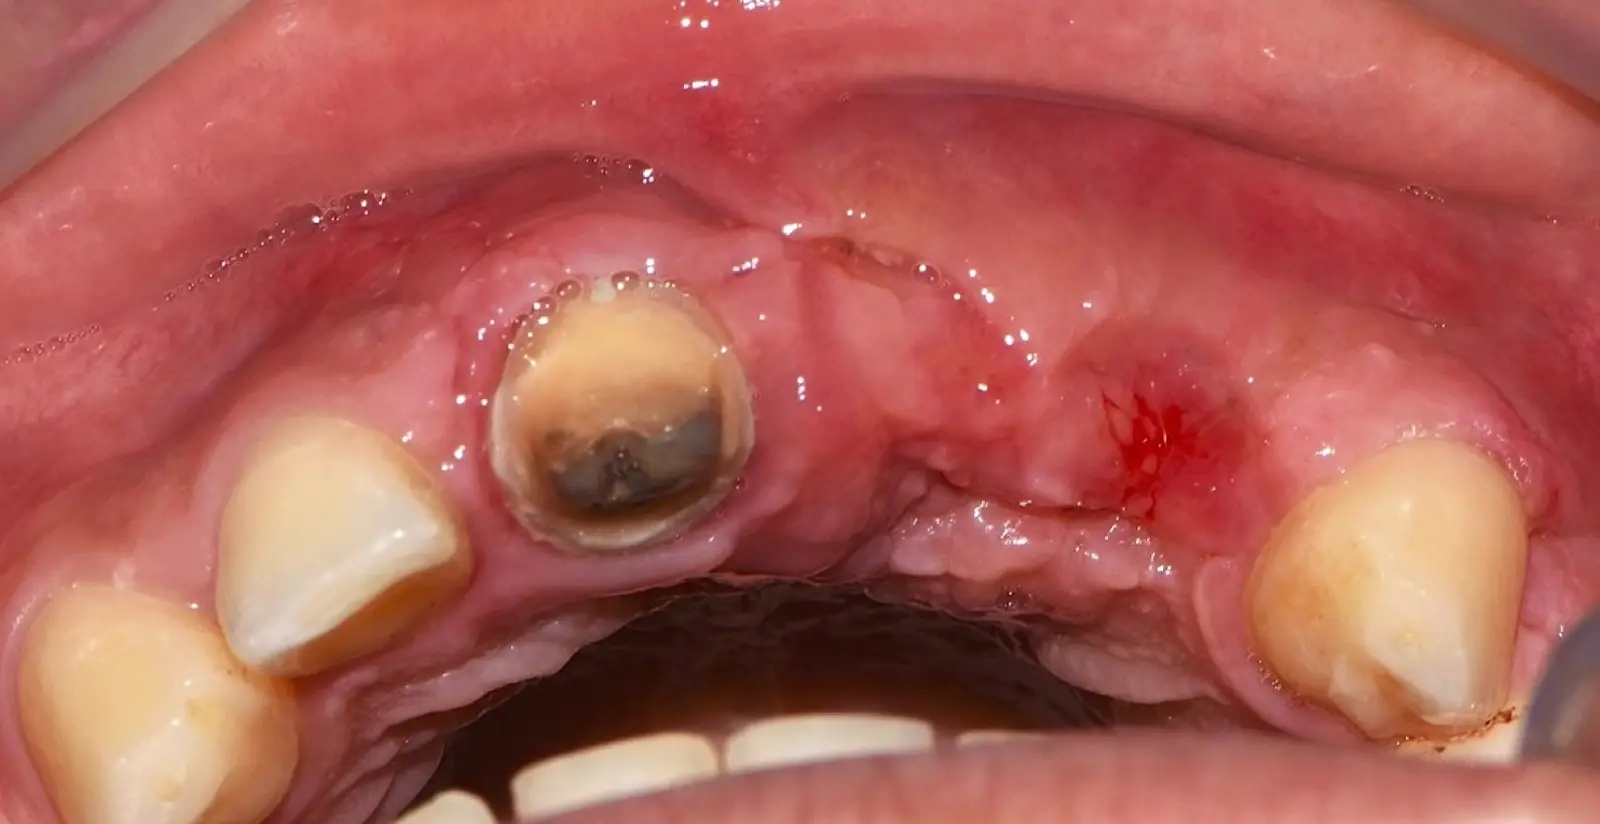

Paciente de sexo femenino de 36 años de edad, llega a la consulta por presentar una restauración protésica inadecuada. En el examen clínico se observa una restauración protésica provisional acrílica sobre las piezas 1.1 y 2.2. Adicionalmente, se aprecia recesión gingival a nivel de la pieza 2.2 y deficiencia horizontal severa de reborde a nivel de la zona edéntula correspondiente a la pieza 2.1. En la evaluación tomográfica se observa ausencia total de tabla ósea vestibular en la pieza 2.2, y se corrobora el déficit en la zona edéntula de la pieza 2.1, para lo cual se indica una reconstrucción de estructuras óseas con hueso en bloque de origen bovino y posteriormente la colocación de implantes dentales.

Figura 35. Decolado a espesor total sobrepasando la línea mucogingival (a, b).

Figura 36. Defecto óseo y severa reabsorción ósea horizontal: vista clínica (a) y corte tomográfico (b).